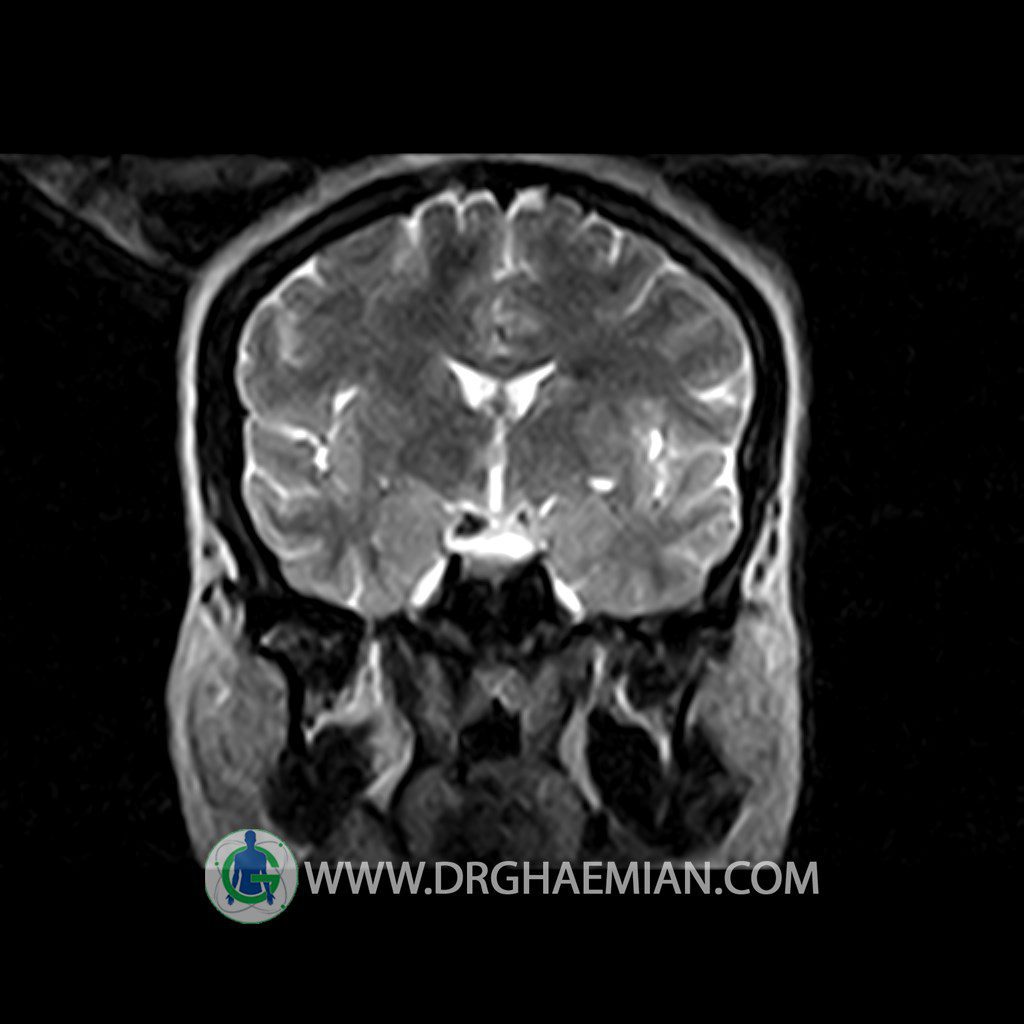

ام آر آی هیپوفیز یک روش تصویر برداری است که از غده هیپوفیز (غده ایی کوچک در مغز که هرومون ها و دیگر غدد بدن را کنترل می کند) و ناحیه های پیرامونش در مغز تصاویری ایجاد می کند. در این کیس سلای نسبتا خالی در ناحیه هیپوفیز بیمار مشاهده می شود.

– Extension of suprasella cistern to sella with thin pituitary gland in floor of sella ( partial empty sella )

is seen